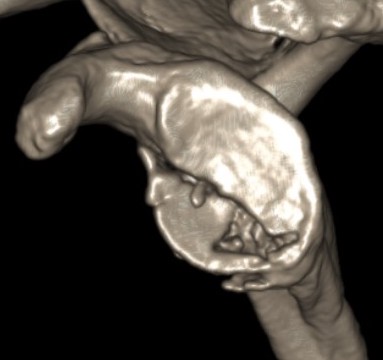

Type II: Fracture glenoid fossa that exits laterally

Definition

Transverse fracture through glenoid fossa

- inferior triangular fragment

- exits lateral border scapula